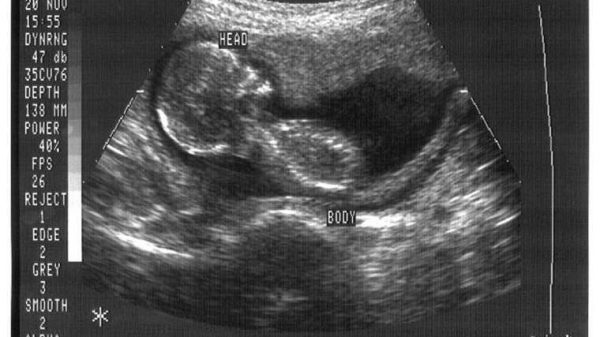

En Iowa, por su parte, el Congreso y el Senado aprobaron el requisito de un período de espera de 24 horas para realizar un aborto. La legislación también requiere que la mujer vea los ultrasonidos del niño no nacido y que reciba información sobre las posibildades de entregar a su hijo en adopción.